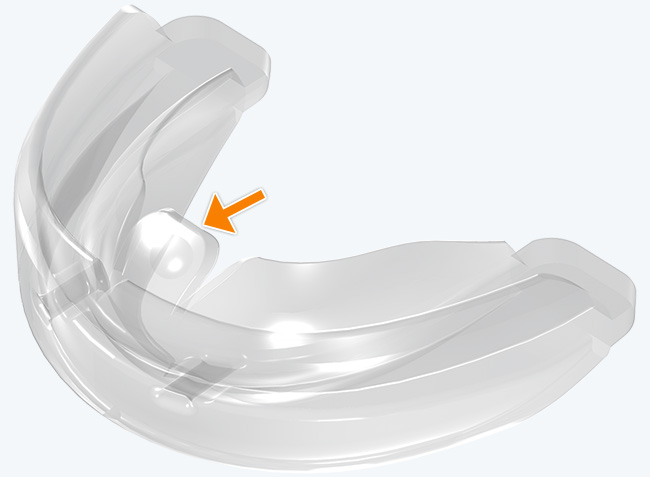

The TMJ Appliance®, which does not require any special fitting, is designed to act as an initial diagnostic and treatment tool for TMJ disorder. It works by decompressing the temporomandibular joint (TMJ), helps to correct mouth breathing and tongue posture habits, as well as limits bruxing. The TMJ Appliance® achieves TMJ disorder symptom relief immediately by alleviating pressure on the TMJ and relaxes the muscles around the jaw and neck.

The TMJ Appliance® treats both intracapsular and extracapsular disorders—TMJ clicking and pain (intracapsular) as well as pain referred from the craniomandibular muscles (extracapsular).